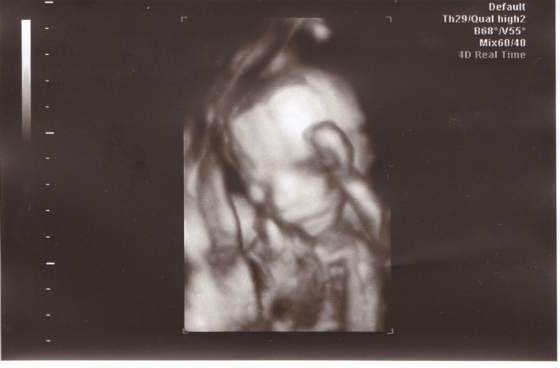

No to teraz nasz Karolek;-)

glowka

W macicy obecny jeden żywy płód w położeniu dowolnym, o wym.:

BPD – 42 mm

HC – 158 mm

AC – 133 mm

FL – 29 mm

odpowiada to 18-19 hbd

Serce czterojamowe FHR (+),plus. Cztery kończyny widoczne. Zarys czaszki i kręgosłupa prawidłowy.

Pęcherz moczowy i żołądek widoczne. Łożysko w trzonie macicy, na ścianie przedniej; I stopien dojrzałości. Aktywność ruchowa płodu prawidłowa.Ilość płynu owodniowego prawidłowa.

Biometria płodu nie jest zgodna z terminem porodu wyliczonym z OM.

Amna, czyli Bobas zdrowy, wszystko na miejscu :-). Gratulacje.